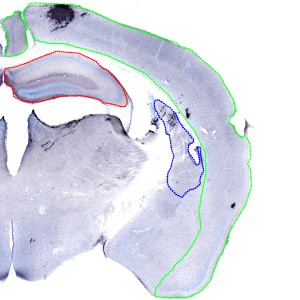

Overview image, showing the outline of regions of interest on the right half of a coronal brain section. Green: Cerebral Cortex, Red: Striatum, Blue: Hippocampus.

The right and left hemisphere of each brain must first be extracted as individual images by using the auxiliary APP for Arrayimager, to allow you to report the results per animal. When the images from each hemisphere have been extracted, the ROIs must be outlined manually as shown in FIGURE 1. Finally the APP for quantification can be applied.